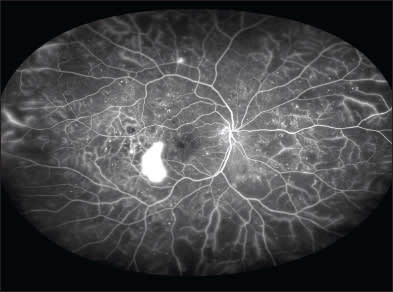

Figure 3. BRVO as demonstrated by widefield angiography. Given that more peripheral nonperfusion is visible, widefield angiography may be able to classify vein occlusions more accurately (imaged with the Optos 200 Tx).

Central and branch RVOs are also starting to be investigated to a greater extent with widefield angiography.26 Similar to diabetic retinopathy, most of the treatment paradigms for these diseases were based on studies completed 20 to 30 years ago. Unlike diabetes, however, vein occlusions were classified as ischemic and nonischemic based on the amount of retinal nonperfusion.

Given the extent of non-perfusion that can be visualized with widefield imaging (Figure 3), it is understandable that more accurate classification could be made with this newer technology. Similar to the above-mentioned study on peripheral diabetic pathology, we may now be able to visualize peripheral nonperfusion or perivascular leakage in RVO that would have been missed with traditional imaging (Figure 4). In fact, some investigators are using widefield angiography to develop an “ischemic index” (amount of nonperfused to total visualized retina) to classify eyes with CRVO better.